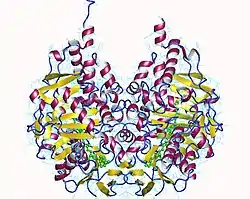

Monoamine oxidase B has a hydrophobic bipartite elongated cavity that (for the "open" conformation) occupies a combined volume close to 700 Å3. hMAO-A has a single cavity that exhibits a rounder shape and is larger in volume than the "substrate cavity" of hMAO-B.[7]

The first cavity of hMAO-B has been termed the entrance cavity (290 Å3), the second substrate cavity or active site cavity (~390 Å3) – between both an isoleucine199 side-chain serves as a gate. Depending on the substrate or bound inhibitor, it can exist in either an open or a closed form, which has been shown to be important in defining the inhibitor specificity of hMAO-B. At the end of the substrate cavity is the FAD cofactor with sites for favorable amine binding about the flavin involving two nearly parallel tyrosyl (398 and 435) residues that form what has been termed an aromatic cage.[7]